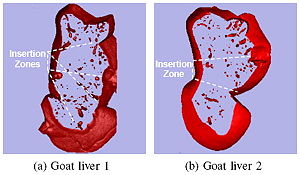

- 5.7 Can Transrectal Needle Biopsy be Optimised to Detect Nearly All Prostate Cancer with a Volume of ≥0.5 mL? A Three-dimensional Analysis

- 5.12 3D Prostate Histology Image Reconstruction: Quantifying the Impact of Tissue Deformation and Histology Section Location